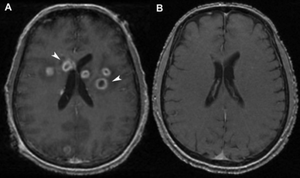

Ring-enhancing lesion

- CT or MRI with lesions having an enhancing ring of contrast around a less dense center can indicate certain neurological infections, injuries, and indolent disorders

- Toxoplasmosis v. lymphoma (see comparison of characteristics at Radiopaedia.org.)